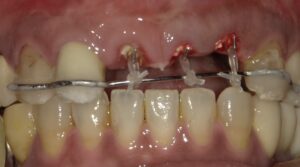

そのため挺出治療を開始しました。ゴムで歯を牽引して

いくものです。

プラスチックを貼って装置をわかりにくくします。